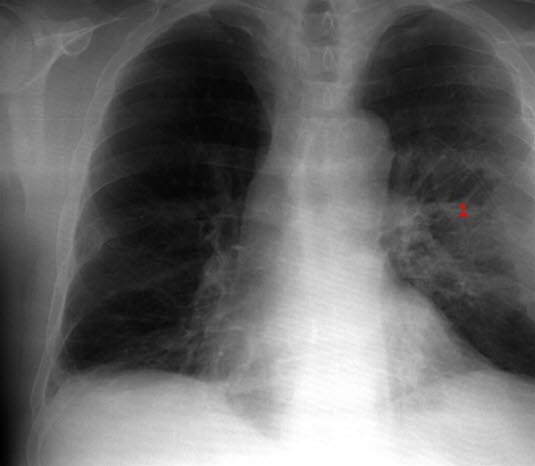

Lungeabscess - etter behandling

Restforandringer etter behandling av lungeabscess (1)